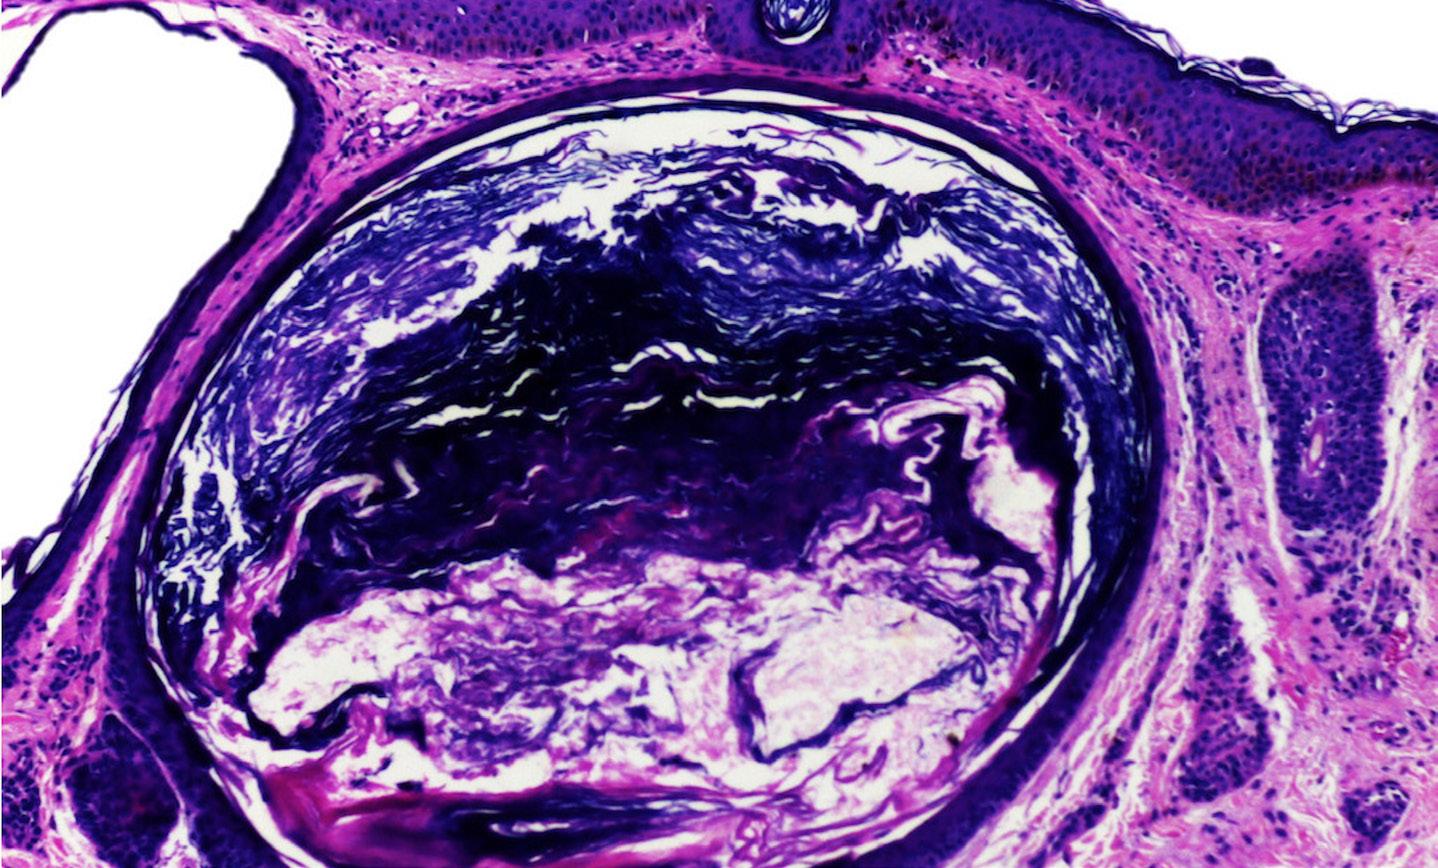

Cisto veloso eruptivo periorbital: tratamento desafiador em localização atípica Periorbital eruptive vellus hair cysts: a challenging

218 Bruna dos Anjos Bortolini, Rafael Cavanellas Fraga, Paulo Sergio Emerich Nogueira, Tiago de Almeida Grippa, Vitor Angelo Ferreira